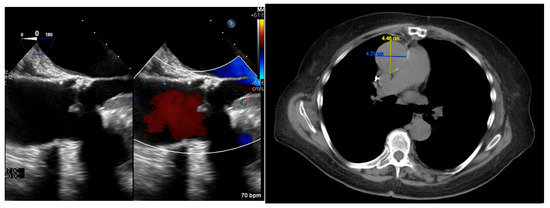

| 9 | 83 | Male | Caucasian | Unknown | p.A3542V | Exon: 2 Codon 3542 | Tolerated | Aortic and celiac aneurysm/dissection |